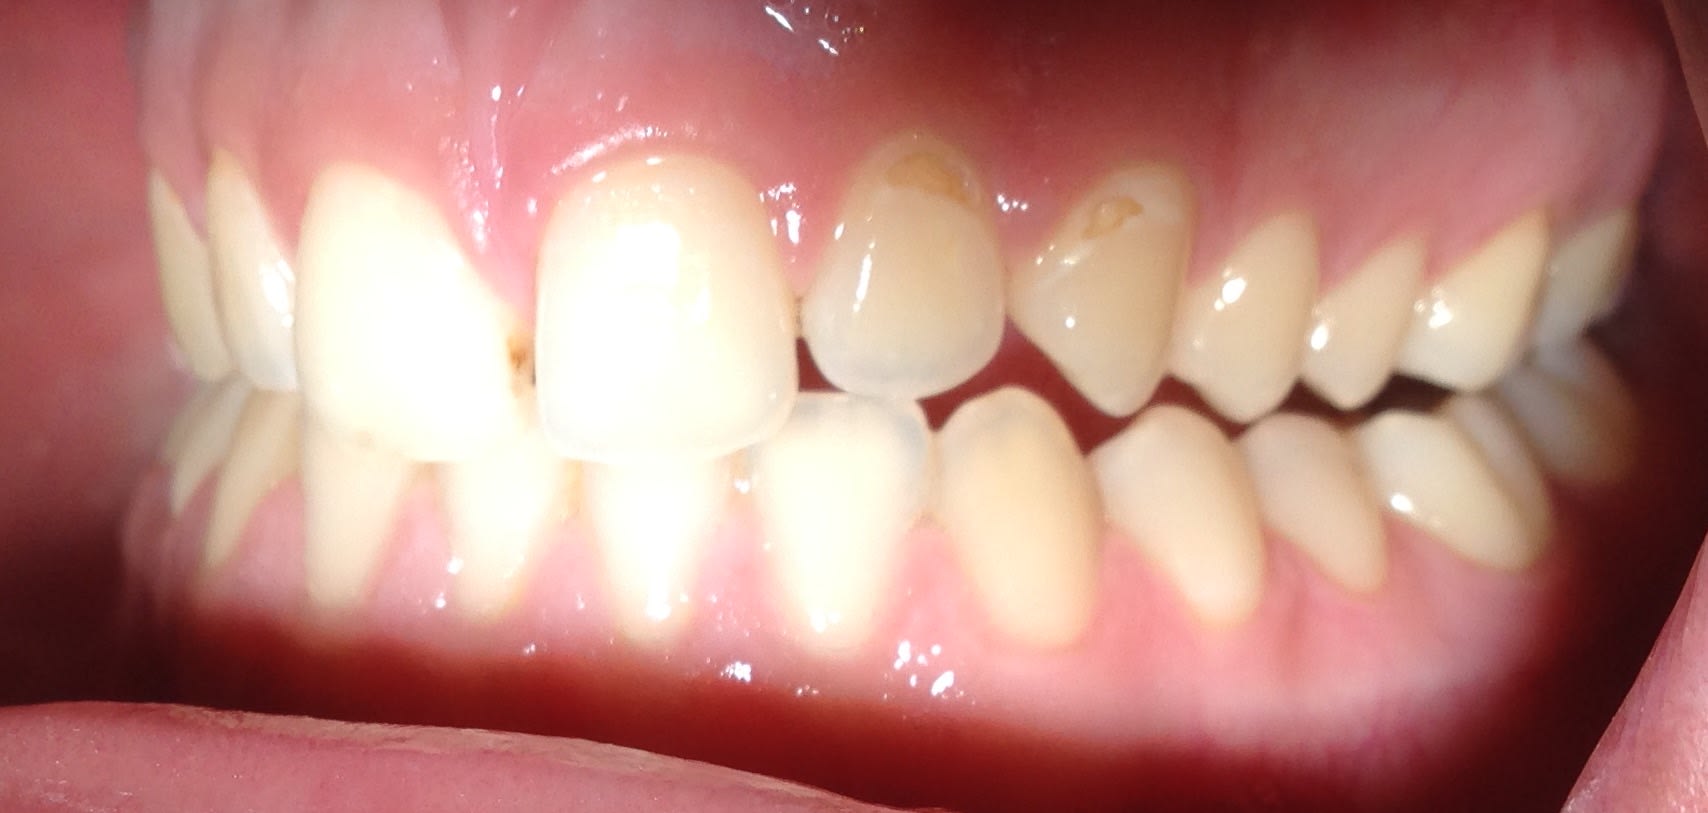

regardez moi ça cette 6 sur Implant réalisée par les chinois que je viens de poser : c'est pas beau ça quand même ? Vraiment Du bon travail. Et juste à coté regardez les CCM réalisées par sans doute des prothésistes français. Y a pas photo : une très nette supériorité en qualité pour les prothésistes chinois.

Quoique ces couillons ne m'ont pas fait de pont d'email, et la cuspide MP devait être plus grosse que la D... j'ai même pas remarqué ça hier 😊 . En même temps,Entre nous c'est pas ça qui va changer grand chose à l'efficacité masticatoire. Ils ont du filer cette 6 au mec qui s'occupe des 6 mandibulaires au lieu de Le donner au mec qui s'occupe des 6 maxillaires .

Enlaye ??? C'est le fameux que je t'avais déjà montré . J'ai repris des photos avec mon phone.... Qui c'est qui disait qu'il ne pouvait pas fermer comme ça ? Rappelle moi voir son nom 😊. On fait moins le malin tout d'un coup ! Alors on sait plus quoi dire ? 😊

Ce que je comprends pas c'est pourquoi En 25 ans ses PM n'ont pas cherché le contact avec celles du bas . Il y a juste des contacts au niveau des 7 et des incisives